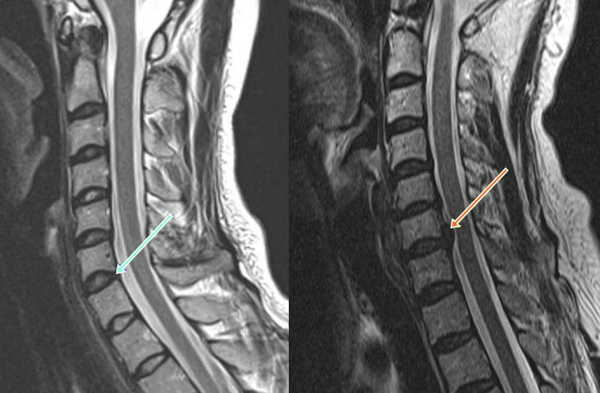

MRI로 영상학적 진단

디스크 질환의 영상학적 진단은 MRI로 한다. 엑스레이를 촬영해 척추 뼈의 간격이나 마모상태를 통해 디스크 상태를 예측할 수 있고, 고해상도 CT의 경우 디스크가 튀어나온 것을 어느 정도 볼 수 있다. 디스크의 상태, 주변 신경과의 관계 등을 종합적으로 볼 수 있는 검사는 MRI다.

그렇다면 의원에서 엑스레이 촬영만 하고 디스크 질환을 진단받았다면 오진일까. 반드시 그렇지는 않다. 이유는 디스크 질환이 영상만으로 완벽히 확진되는 질환이 아니기 때문이다. 증상이 전혀 없이 지내던 환자에게서 디스크 내장증이 발견되기도 하고, MRI상 디스크 질환이 보이나 실제로 환자가 호소하는 증상과 맞지 않는 경우도 많다. 즉, 모든 요통의 원인이 디스크는 아니라는 것이다.

반대로 퇴행성 디스크 질환이 있는 환자의 경우 정도가 심해 신경이 지나가는 길이 좁아지는 '척추관 협착증'이 동반돼 있는 경우, 증상이 무릎 아래까지 내려가기도 한다. 따라서 추간판 조영술이나 근전도 검사와 같은 추가적인 검사가 필요하기도 하다. 무엇보다 다양한 진찰 및 검사를 통한 접근방법이 필요해 꾸준히 진료를 통해 자신의 병에 대해 알아가는 것이 중요하다.